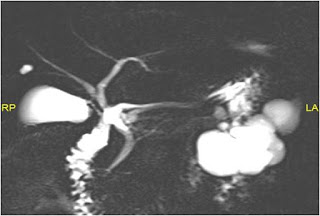

Figure C: Magnetic Resonance Cholangio-Pancreatography

In our patient, the contrast enhanced abdominal computed tomography scan shows a lobulated cystic neoplasm with septations in the body and tail of pancreas with thin (< 2 mm) non enhancing walls. The cystic spaces (6 in number) are > 2 cm (Figure A). These findings are better appreciated in contrast enhanced abdominal magnetic resonance imaging scan (Figure B). At magnetic resonance cholangio-pancreatography (MRCP), the main pancreatic duct (MPD) is not dilated in its entire course and there was no duct – cyst communication (Figure C). Hence a diagnosis of SOA was made.3

Branch chain IPMN was ruled out as the MPD was of normal caliber at MRCP and the cystic tumor did not have communication with the main pancreatic duct (Figure B).